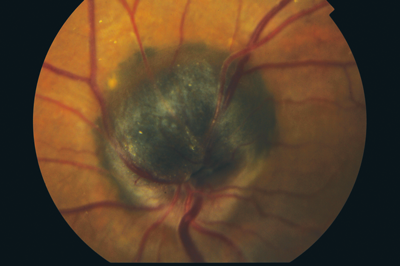

On examination, visual acuity was 6/6 in the right and 6/6 in the left. Ocular movements were full, there was no diplopia in any position of gaze. Anterior segment examination was normal with the pupils reacting equally to light on both sides. On dilated ophthalmoscopy the right retina was normal. The left retina revealed an elevated pigmented lesion over the optic disc. The lesion was measured using B scan ultrasonography and found to be 2.4mm x 1.7mm. The clinical appearance of the lesion was consistent with a diagnosis of melanocytoma.

Figure 1: Optic disc melanocytoma.